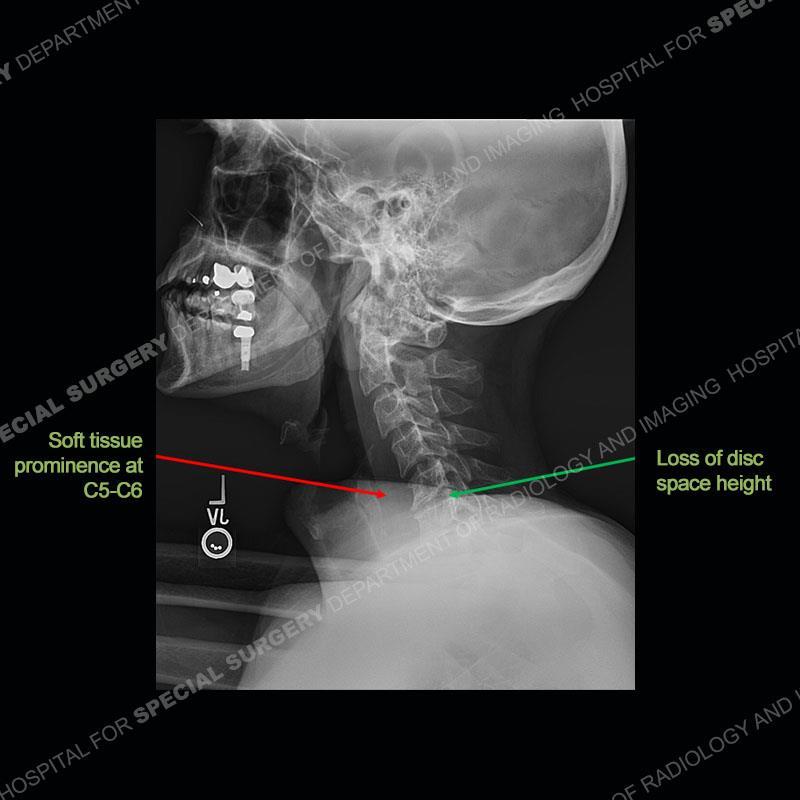

The radiographs demonstrate a prevertebral soft tissue fullness centered at C5-C6 that persists even on extension. There is a slight loss of disc height at C5-C6. The CT more readily shows the prevertebral soft tissue swelling at C5C6 where there is a punctate focus of gas. On the MRI, there is a marked amount of edema and a heterogeneous collection in the prevertebral soft tissue at C5-C6. Edema is present of the C5 and C6 vertebral bodies with a loss of the normal architecture about the disc space. A heterogeneous epidural collection has formed that causes compression of the spinal cord asymmetric to the left side and also precipitates severe left sided neural foraminal stenosis.